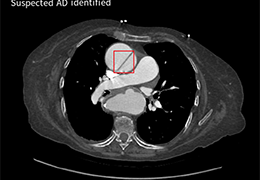

成像智能。

Eclipse 成像智能功能提供强大的处理能力和最佳质量的影像,同时减少质量错误并提高剂量效率。

凭借 AI、专有算法和先进的影像处理能力,提供出色的影像质量和无与伦比的诊断信心。